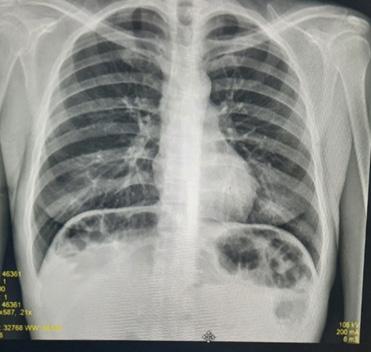

Neurofibromatosis tipo I en paciente femenino y su manejo multidisciplinario

Neurofibromatosis type 1 in a woman patient and its multidisciplinary management

Pablo Aparicio, Jamil Machicao................................................................................................................73-80